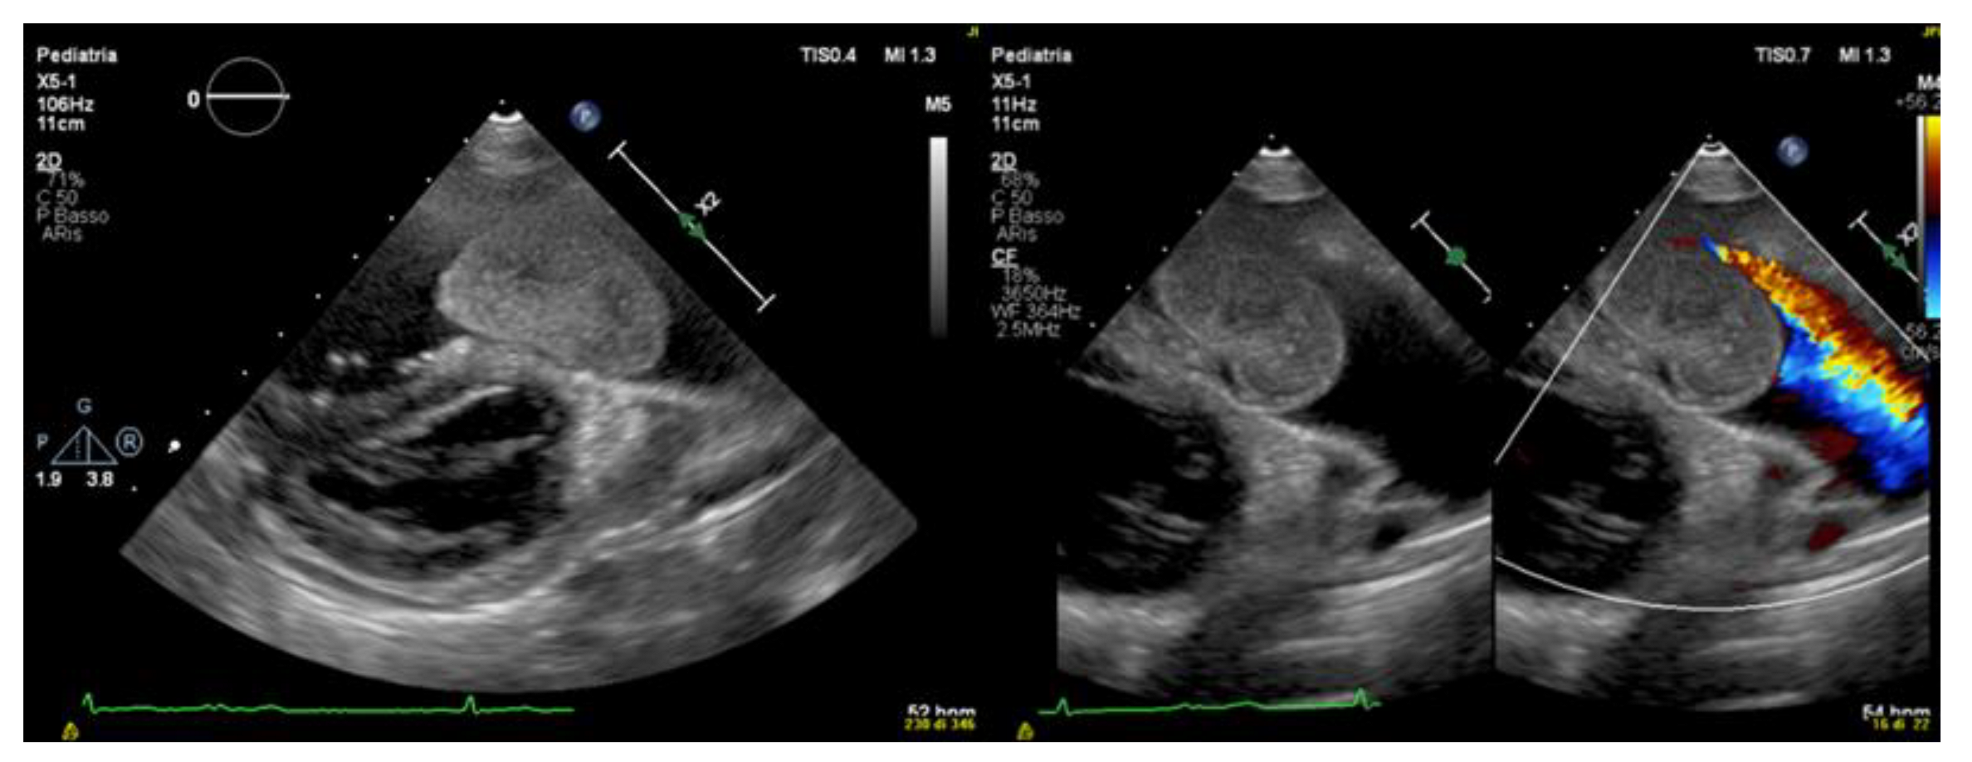

ECG revealed sinus rhythm with normal PR and QTc intervals, right bundle block with ventricular repolarization abnormalities in the right leads and isolated monomorphic premature ventricular contractions (PVCs), often organized in bigeminy rhythm (Figure 1).

The ECG shows PVCs arising likely from the pulmonary artery/free wall of the right ventricular outflow tract. An LBBB configuration with inferior axis is seen with late precordial transition after V3 and QS in V1 e rS in lead I.